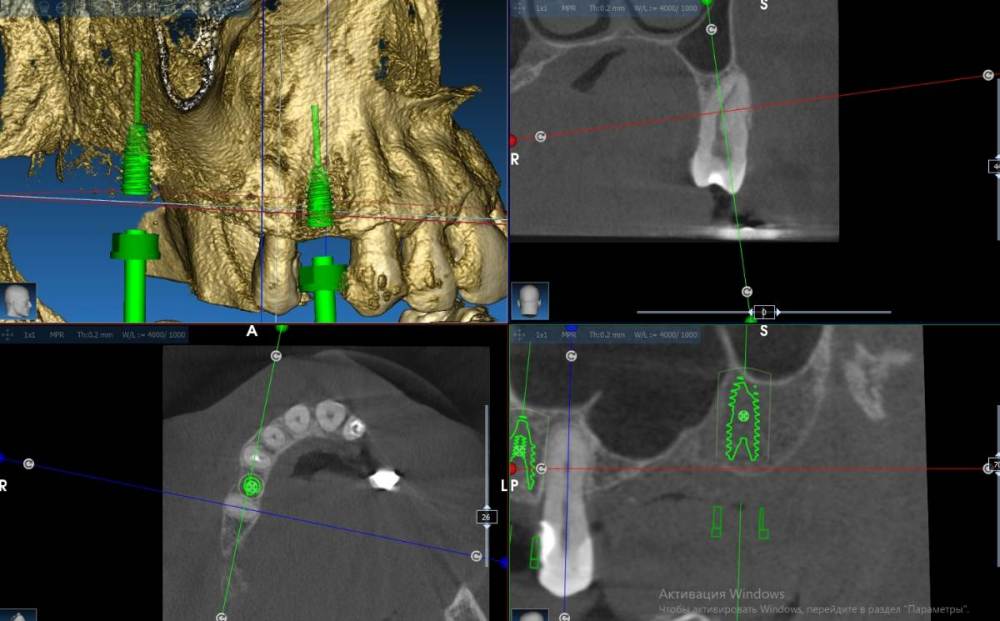

Fin Опубликовано 16 декабря, 2021 Автор Поделиться Опубликовано 16 декабря, 2021 3 часа назад, Irouil сказал: Если зуб витальный и без выраженной патологии, то как может быть его лучше заменить на имплант? Возможность избежать синуса того явно не стоит, имхо Имел ввиду что так проще, чем мудрить что то новое. Выраженных показаний нет, только небольшая атрофия. Наконец добрался до КТшки. Ссылка на комментарий